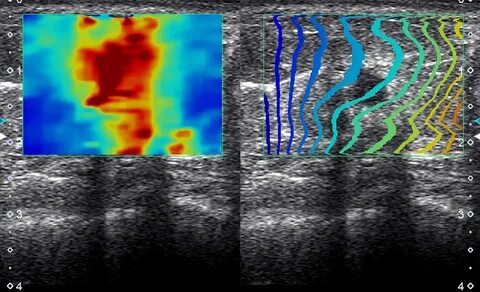

If you're not already using elastography imaging in your liver diagnostics, you're probably considering it. This non-invasive technique measures liver stiffness—a key indicator of fibrosis and cirrhosis. Instead of relying on painful biopsies, we’re now seeing clear, quantifiable results through real-time imaging.

The imaging delivers quantitative data in seconds. That means faster diagnoses, fewer false negatives, and more confident decision-making—all without making your patient uncomfortable.

• Provides immediate visual and numerical results

• Improves accuracy over traditional ultrasound or CT